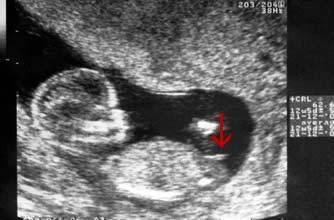

怀孕十三周胎儿性别图

怀孕十三周胎儿性别图,十六周胎儿性别区别图

反之就是女宝; 十一至十三周,所有的胎儿都会在双腿之间长出一个小

孕16周,四维b超能看清楚胎儿性别吗